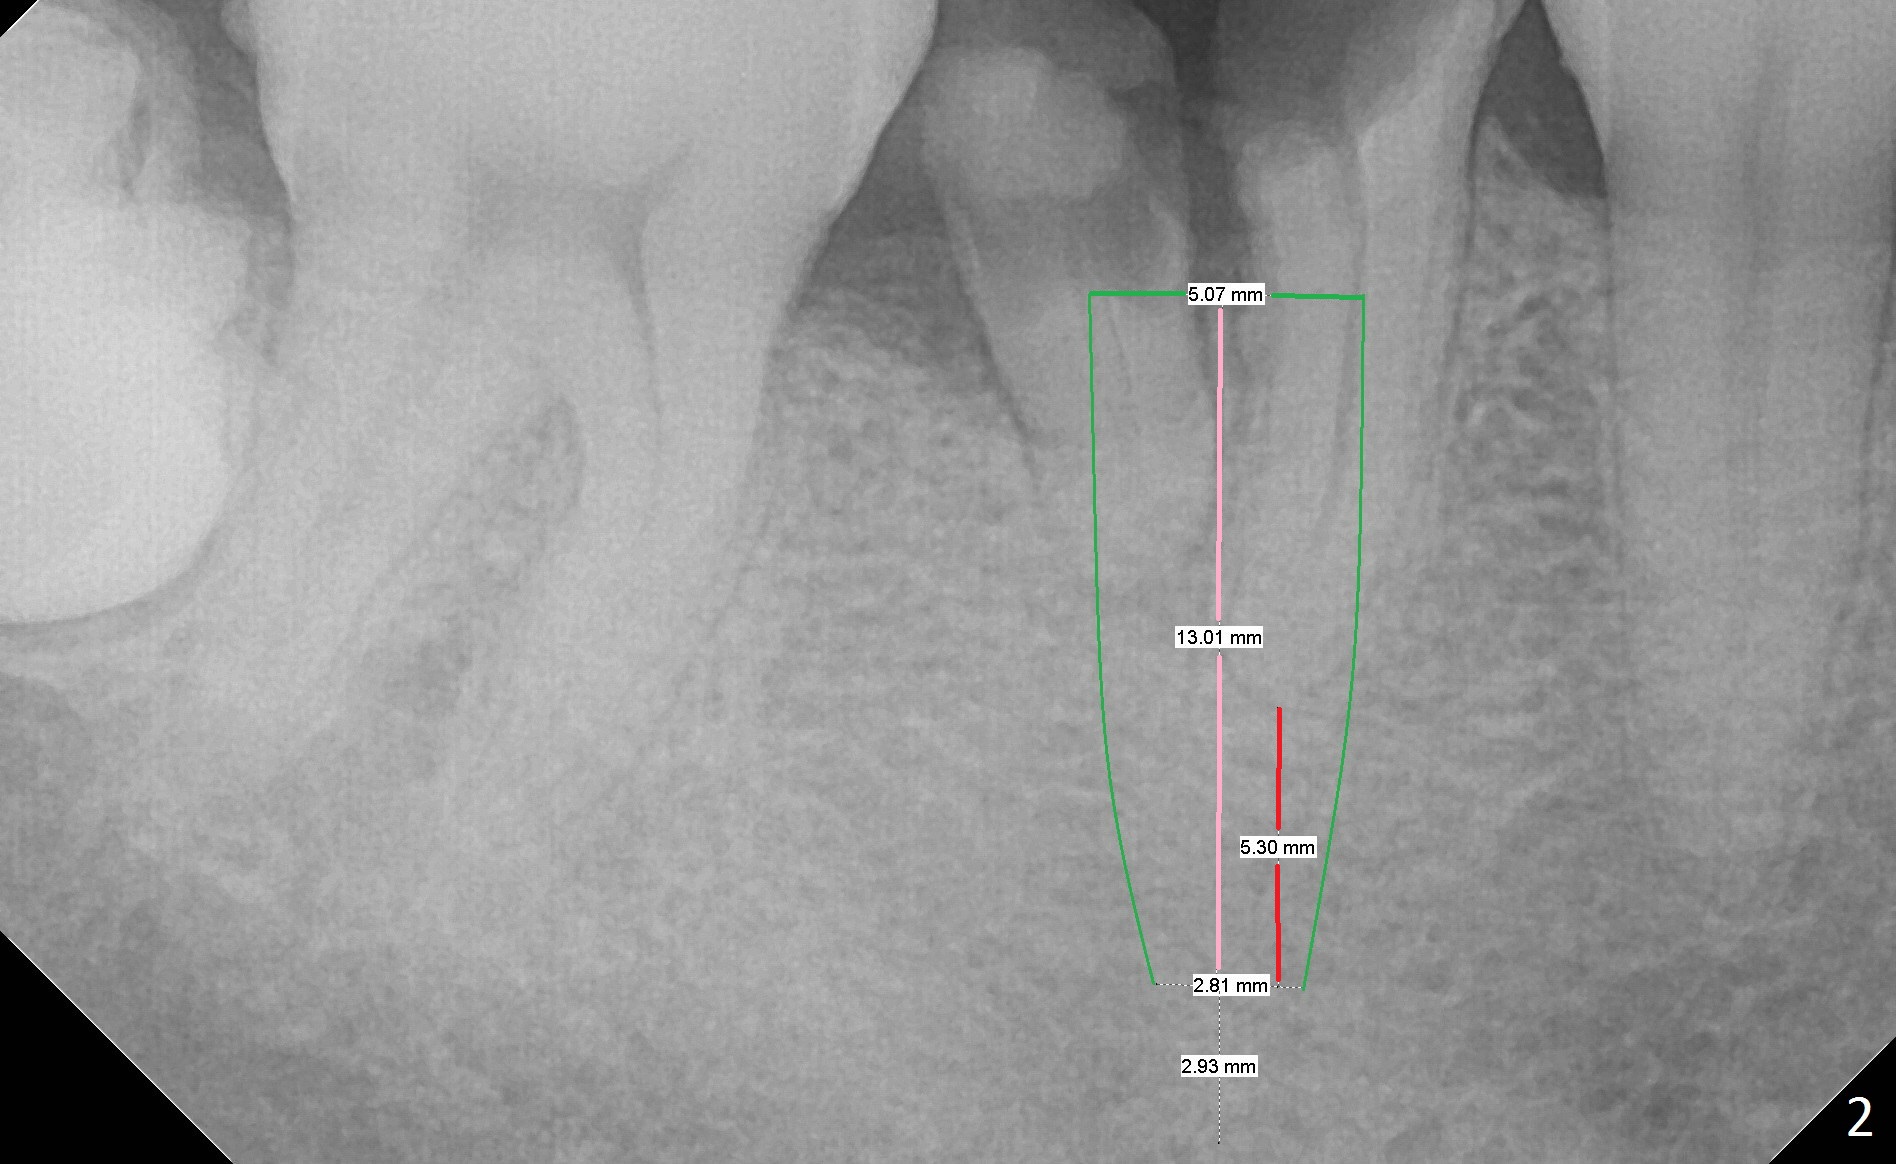

A 43-year-old man has residual roots at #30 (Fig.1). The mesial (M) and distal (D) roots approximates each other so close that the septum is thin (Fig.1,3-5). The latter is unfavorable for osteotomy. After extraction (Fig.5), the middle of the septum (Fig.8a (axial section of the sockets)) will be sectioned (Fig.6, 8b,c) prior to initial osteotomy (Fig.7,8d). The depth of the latter will be ~ 5 mm (Fig.2 red line) for a 13 mm (pink line) IBS implant.